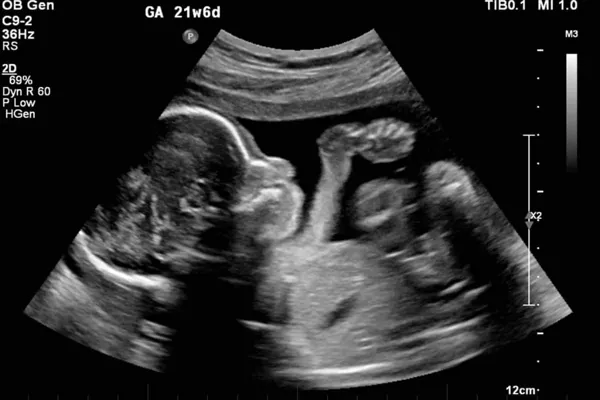

معاینه اولتراسوند: در طول سونوگرافی بیوفیزیکال ، روی تخت معاینه دراز کشیده اید. ارائه دهنده دستگاهی به نام مبدل (یا پروب) را روی شکم شما حرکت می دهد تا امواج صوتی تولید کند. مبدل امواج صوتی را به تصاویری تبدیل می کند که می توان آن ها را روی صفحه نمایش مشاهده کرد.

تست بدون استرس NST: در حالی که روی تخت دراز کشیده اید برای سونوگرافی بیوفیزیکال ، یک مانیتور الکترونیکی، ضربان قلب جنین را اندازه گیری می کند.

مسئول مربوطه یک کمربند با یک سنسور الکترونیکی در اطراف شکم شما قرار می دهد. سپس سنسور ضربان قلب جنین را اندازه گیری و ثبت می کند. این آزمایش معمولاً حدود 20 دقیقه طول می کشد، اما بسته به فعالیت جنین می تواند تا 40 دقیقه ادامه یابد.